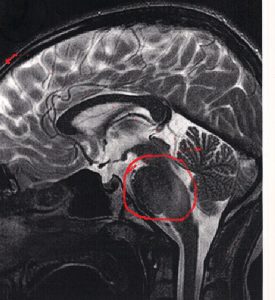

Dlatego podświetlone obszary, które wyłoniły się z cienia na zdjęciu rezonansu- bardzo nas zaskoczyły i zmartwiły.

Dlatego podświetlone obszary, które wyłoniły się z cienia na zdjęciu rezonansu- bardzo nas zaskoczyły i zmartwiły.

Na zdjęciach widać to tak : ten z lewej najjaśniej świecący- to potwór z 25.05.2018 i takiego go zobaczyliśmy po raz pierwszy. Po naświetlaniach w zasadzie całkiem zniknął, ateraz wyłania się powoli z cienia jak zły duch…

The last MRI scan, the moment of truth, as we call it, always cause a huge amount of stress. This time we were very optimisti on our way to Warsaw to undergoe the tests. The last results from immunotherapy in Cologne were excellent, and if the therapy is going great then it should be the opposite fo the tumor. That is why the highlightened areas on Jasius scan came as a surprise and worried us alot.

The photos shows: the first photo is from w got the diagnosis, the bright region is the moster we are fighting with since may last year…it almost dessapeared after radiotherapy and now is emerging from the shadows again…